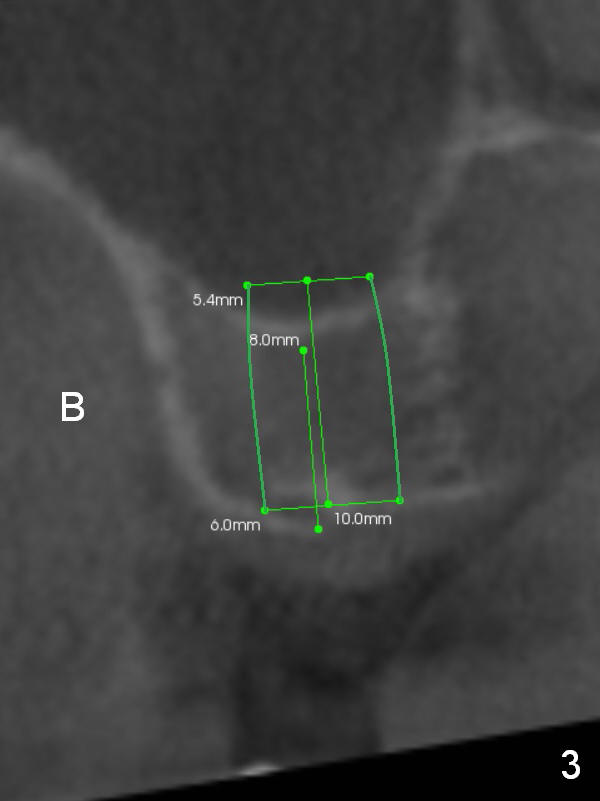

To handle the 2nd challenge, start bone expansion with #15 and osteotomes (from 8 to 11 mm). Set implant spacer at 4 mm (Fig.2). Prepare allograft (.5-1 mm) and Osteogen (4:1 ratio) for sinus lift. Place 8 mm stopper on the larger condenser from Sinus Master Kit.